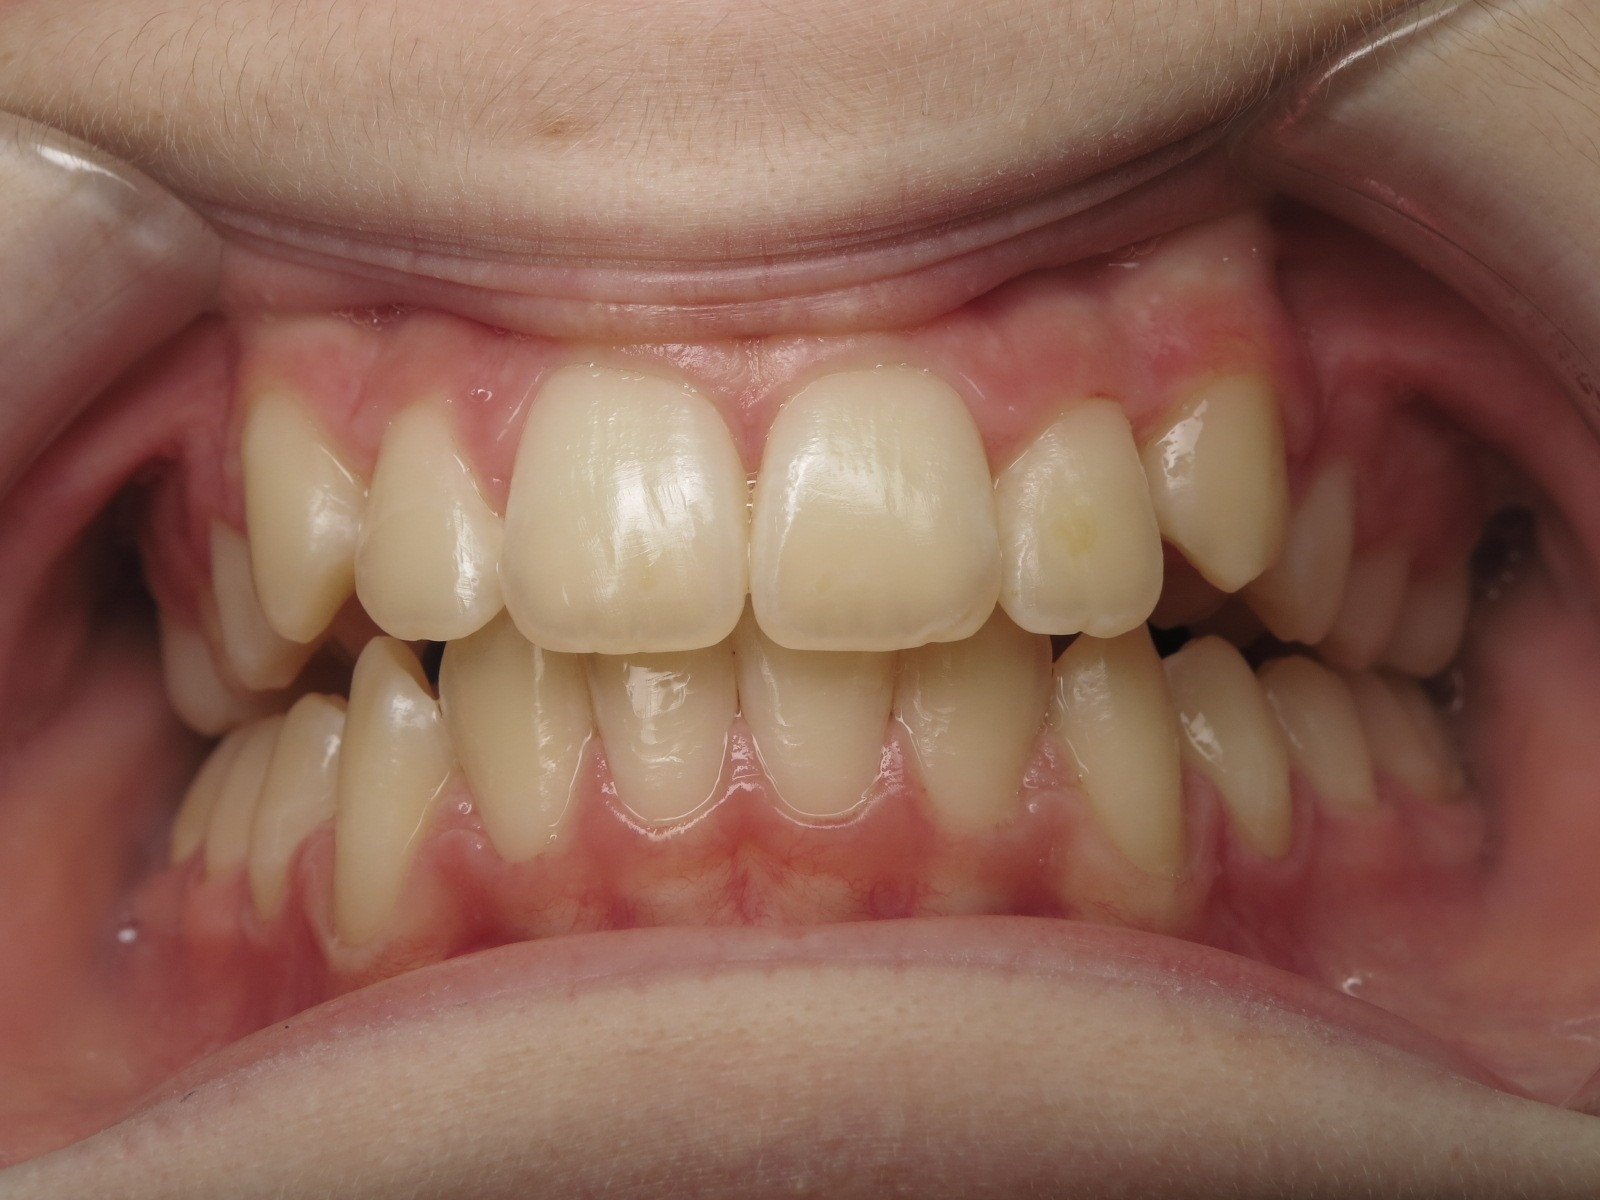

surveillance évolution de la dentition pendant 4 ans

bilan début fin de traitement